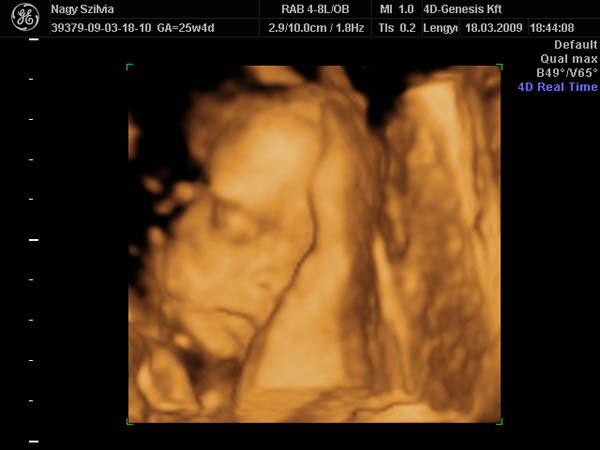

De szép nagy fiad van